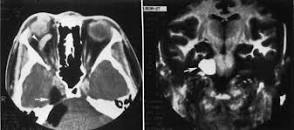

Persistent trigeminal artery. Axial T2-weighted imaging (a) and CT angiography (b). Vascular channel connecting the left internal carotid artery and the basilar artery, and running through the medial aspect of Meckel’s cave

Trigeminal AVM. A 58-year-old man with right facial neuralgia. Axial T2 (a) and axial C+ (b) showing abnormal serpentine vasculature along cisternal segment of right CN V extending into Meckel’s cave on DSA (c)—arteriovenous shunting from right anterior inferior cerebellar artery (AICA) with prominent draining vein